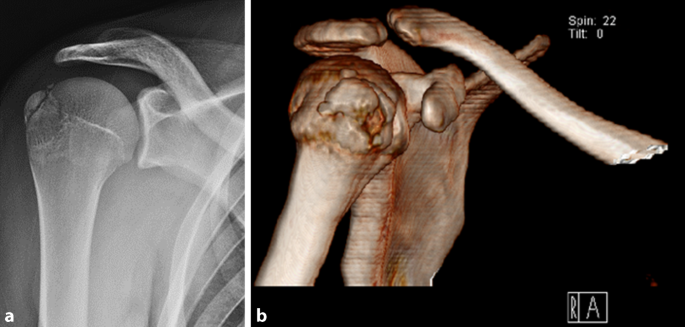

Abb. 1 8 Eine 85-jährige Patientin mit 4-Part-Fraktur des proximalen... | Download Scientific Diagram